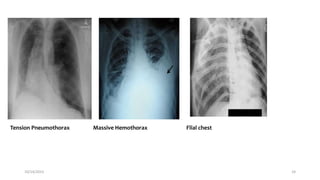

Tension Pneumothorax Massive Hemothorax Flial chest

Breathing Interventions

Ventilate with 100% oxygen

Needle decompression if tension pneumothorax suspected

Chest tubes for pneumothorax / hemothorax

Occlusive dressing to sucking chest wound

If intubated, evaluate ETT position